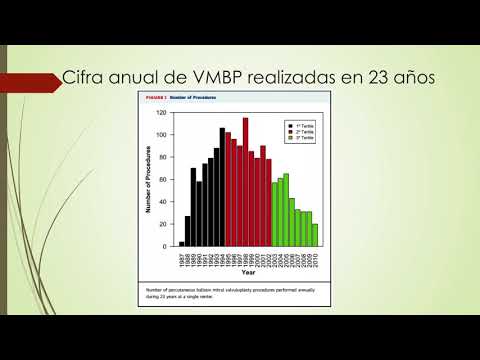

Seguimiento prolongado en pacientes post valvuloplastía mitral con balón percutáneo. Dra. María Victoria Vannoni. Residencia de Cardiología. Hospital C. Argerich. Buenos Aires